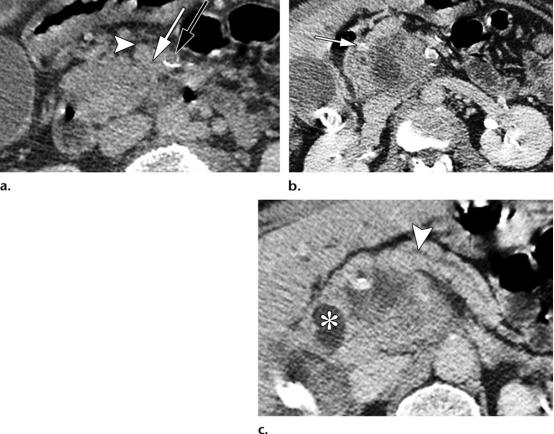

49岁女性,胰腺头部的肿块形成型慢性胰腺炎。

(a图)轴位CT示扩张的主胰管(白色五角形),胰腺实质完整保存,未见明确萎缩。胰管与胰腺实质的比值小于0.5,胰腺实质内可见散在钙化灶(白色短箭头);

(b图)冠状位CT图示,胰头区肿块样病变(白色圆圈),胰管突然变窄,并穿透于实质内(黄色长箭头)。

56岁男性,胰头区的胰腺导管腺癌(PDAC)。

(a图)轴位CT图示肠系膜上静脉(白色短箭头)与肠系膜上动脉(黑色长箭头)大小相仿,伴血管周围的软策划密度包裹(白色长箭头)。肠系膜上静脉的轮廓异常。

(b图)轴位CT图示,胰头区局灶浸润性低密度肿物,侵及胃十二指肠动脉(白色长箭头)。

(c图)轴位CT图示远端胰管的管径正常,胰腺实质也保存完好(白色短箭头),注意观察扩张的胆总管远端(白色*),未见胰腺实质背景的钙化。